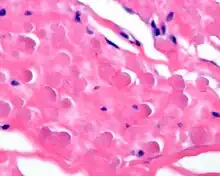

A high power photomicrograph of an elastofibroma.

By microscopie view, there is an admixture of heavy dense bands of collagenous tissue dissected by fat and abnormal elastic fibers. The elastic fibers are often quite large and are easily identified. The elastic fibers are coarse, thick, and darkly eosinophilic, often fragmented into globules, creating a "string of pearls" or "pipe cleaner" appearance. Because of degeneration, the elastic fibers will appear as globules with a serrated or "prickled" edge.[4]